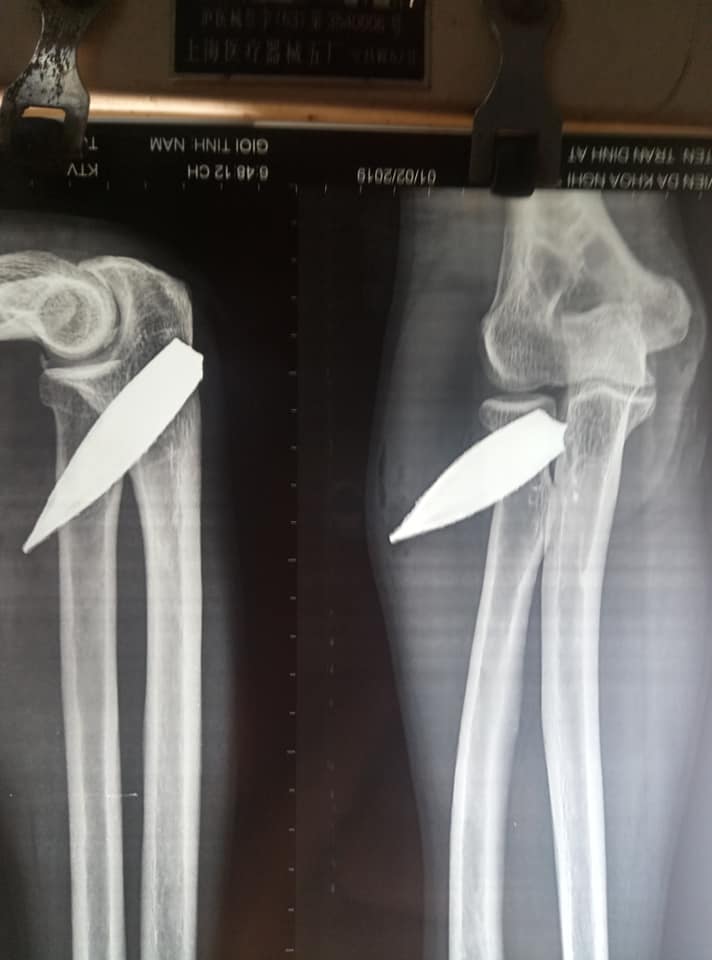

Vào khoảng 19h ngày 1/2/2019 tức 27/12 âm lịch, bệnh Nhân Nam 44 tuổi quê quán Xuân Hông, Nghi Xuân, Hà Tĩnh. Bệnh nhân vào viện cấp cứu sau vụ tai nạn ngã từ độ cao 4m xuống tường rào gây chảy máu và đau nhiều ở khuỷu tay phải. Sau khi khám xét và làm xét nghiệm cận lâm sàng phát hiện bệnh Nhân bị vết thương mặt sau khuỷu tay Phải dài 1,5 cm rỉ máu đau nhức nhiều giảm vận động, chụp Xquang thấy hình ảnh dị vật kim khí mặt sau khuỷu tay phải. Kíp trực đã tiến hành hội chẩn và Chỉ định phẫu thuật lấy mảnh kim khí. Cuộc phẫu tiến hành ngay sau đó lẫn ra dị vật mảnh kim khí dài 7cm*2cm đầu nhọn đầu tù. Sau xử trí bệnh Nhân đã ổn định và được theo dõi tại khoa ngoại Bệnh viện đa khoa huyện Nghi Xuân.

Phim XQ